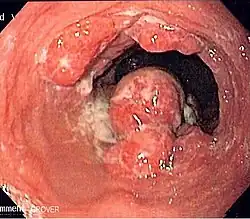

Anatomy

- Length is about 25 cm. Esophageal lesion distance on EGD is typically given from incisors

- Clinically important distance is from incisors to GEJ, which is ~40 cm.

- Layers:

- Mucosa: epithelium, lamina propria, muscularis mucosa. Separated by basement membrane from rest of esophageal wall

- Submucosa: fibroelastic fibers, nervous plexuses, glands

- Muscularis propria: inner circular muscle layer, outer longitudinal muscle layer

- Adventitia: dense periesophageal connective tissue

- The serosa only lines the intra-abdominal esophagus